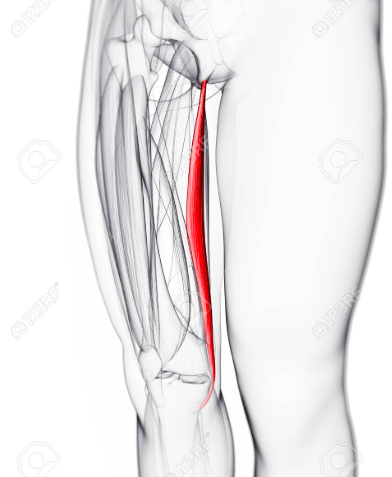

The blood supply for this muscle.

Medial circumflex artery